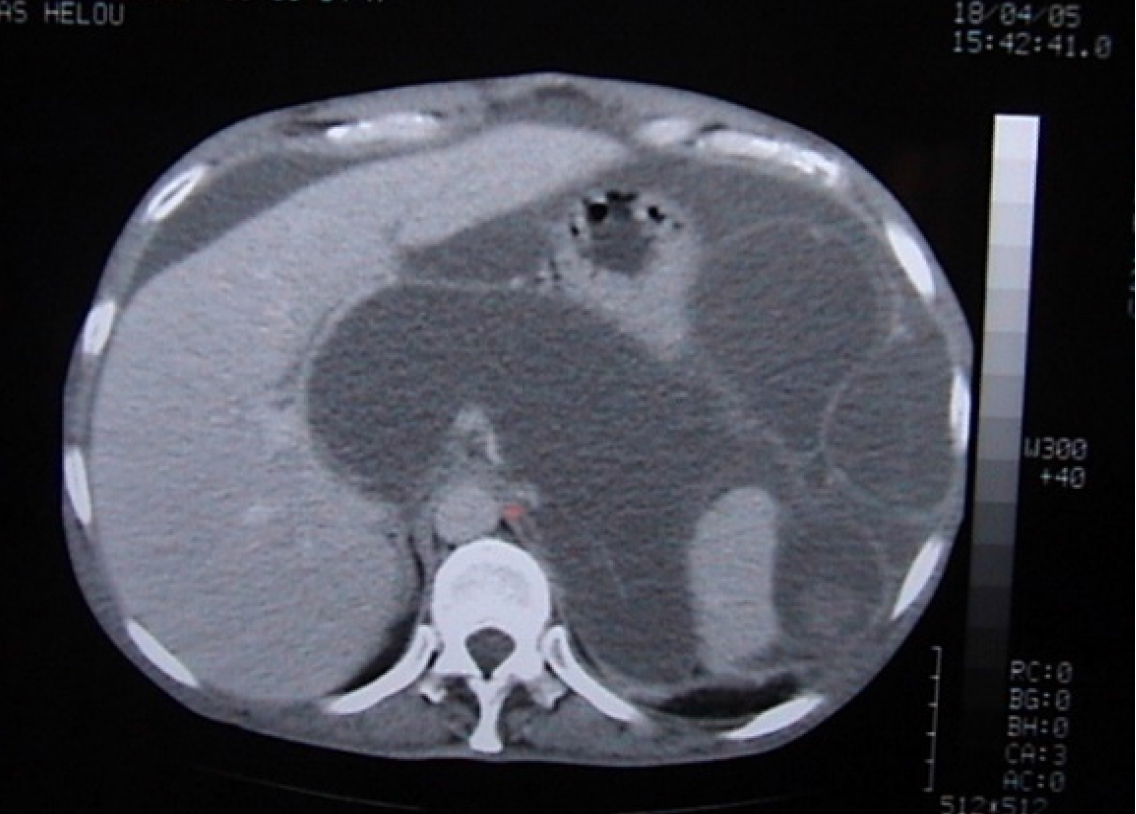

Figure 4 Enhanced computed tomography scan of the abdomen and pelvis.

A: Scalloping of the liver surface; B: Omental caking.